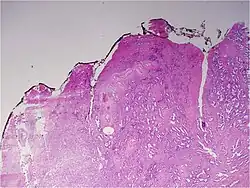

Most often, a urologist or radiologist will remove a cylindrical sample (biopsy) of prostate tissue through the rectum (or, sometimes the perineum), using hollow needles, and biomedical scientists in a histology laboratory prepare microscope slides for H&E staining and immunohistochemistry for diagnosis by a pathologist. If the prostate is surgically removed, a pathologist will slice the prostate for a final examination.

A pathologist microscopically examines the biopsy specimen for certain "Gleason" patterns. These Gleason patterns are associated with the following features:

- Pattern 1 – The cancerous prostate closely resembles normal prostate tissue. The glands are small, well-formed, and closely packed. This corresponds to a well differentiated carcinoma.

- Pattern 2 – The tissue still has well-formed glands, but they are larger and have more tissue between them, implying that the stroma has increased. This also corresponds to a moderately differentiated carcinoma.

- Pattern 3 – The tissue still has recognizable glands, but the cells are darker. At high magnification, some of these cells have left the glands and are beginning to invade the surrounding tissue or having an infiltrative pattern. This corresponds to a moderately differentiated carcinoma.

- Pattern 4 – The tissue has few recognizable glands. Many cells are invading the surrounding tissue in neoplastic clumps. This corresponds to a poorly differentiated carcinoma.

- Pattern 5 – The tissue does not have any or only a few recognizable glands. There are often just sheets of cells throughout the surrounding tissue. This corresponds to an anaplastic carcinoma.

In the present form of the Gleason system, prostate cancer of Gleason patterns 1 and 2 are rarely seen. Gleason pattern 3 is by far the most common.

The Gleason grade is based on tissue architectural patterns rather than purely cytological changes. These tissue patterns are classified into 5 grades, numbered 1 though 5. Lower numbers indicate more differentiation, with pattern 5 being the least differentiated.[4][7] Differentiation is the degree to which the tissue, in this case the tumor, resembles native tissue. Greater resemblance (lower grade) is typically associated with a better prognosis.

However, the Gleason score is not simply the highest grade (least differentiated) pattern within the tumor. Rather, it is a combination of the most two most frequent patterns seen. This recognizes that prostatic carcinomas have multiple patterns and that prognosis is more accurately determined by adding the scores of the two most prevalent patterns. Using this system, the grades of the most prevalent and second most prevalent patterns (if at least 5% of the total), are added together to yield the overall Gleason score.[4][7]

Cytological differences between normal prostate and neoplastic glands are evident in changes to the typical two cell layers of the gland. In prostatic adenocarcinoma, the basal (bottom, usually cuboidal type) cell layer is lost, with only the top layer (usually columnar to pseudostratified) remaining.